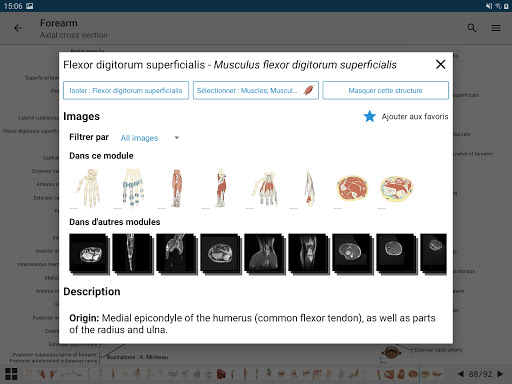

* تحسين عرض التفاصيل للأجزاء التشريحية لتسهيل التعرف عليها في صور الوحدات الحالية والوحدات الأخرى.

- "التصفية حسب" ، في عرض التفاصيل ، يمكنك الآن تصفية الصور التي تحتوي على الهيكل التشريعي حسب الطريقة

- "التصفية حسب" ، في عرض التفاصيل ، يمكنك الآن تصفية الصور التي تحتوي على الهيكل التشريعي حسب الطريقة